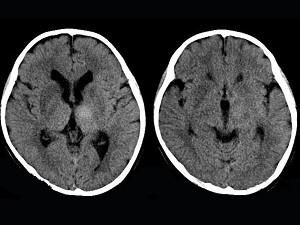

问题 女,12岁,进行性肢体震颤1年余,多次出现发音困难,CT、MRI检查如图所示,最可能的诊断为 ( )

选项 A、脱髓鞘改变 B、脑积水 C、脑萎缩 D、双侧基底节区多发梗死 E、肝豆状核变性

答案 E